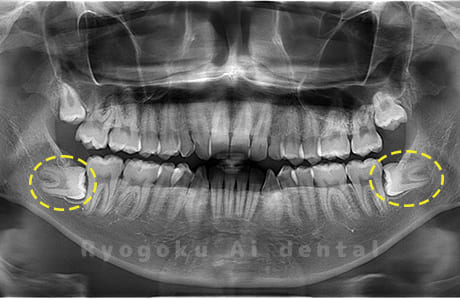

斜めに生えている親知らず

親知らずが斜めに生えて隣の歯にぶつかって圧迫してしまうタイプです。

このタイプが最も多いです。このタイプは虫歯になりやすいだけでなく、隣の歯を圧迫し、咬み合わせや歯並びに影響が出る場合もあるので抜歯をおすすめします。